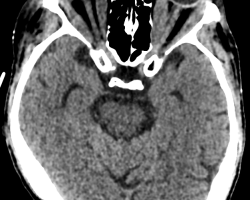

TDM sans injection en coupes axiale et coronale

Présence de gros muscles droits (médial, latéral, supérieur et inférieur) aux deux yeux. Exophtalmie œil droit grade 2, exophtalmie grade 1 pour l’œil gauche (suivant la ligne bicanthale externe). Hypertrophie de l’ensemble des muscles oculomoteurs compatibles avec une maladie de Basedow. Epaississement diffus des muscles oculomoteurs pré dominants sur le droit médial et inférieur